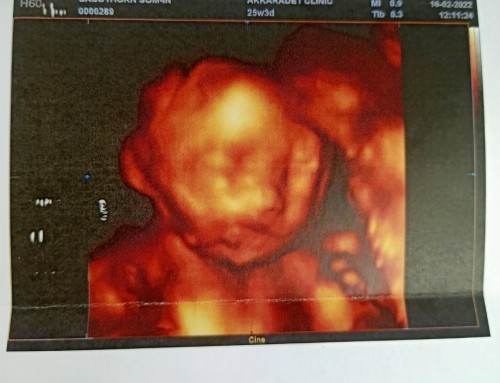

ได้เจอหน้าครั้งแรก

อัลตร้าซาวด์ 25week3day ตื่นเต้นมากได้เห็นหน้าลูกชายแบบ3มิติครั้งแรกค่ะ กำหนดคลอด29พ.ค.65 น้ำหนัก 740กรัม น้องแข็งแรงดี ดิ้นเก่งด้วย น้ำหนักแม่ขึ้นมา9กก.แล้วค่ะ ทีมพ.ค.เป็นยังไงกันบ้างคะ👶🥰